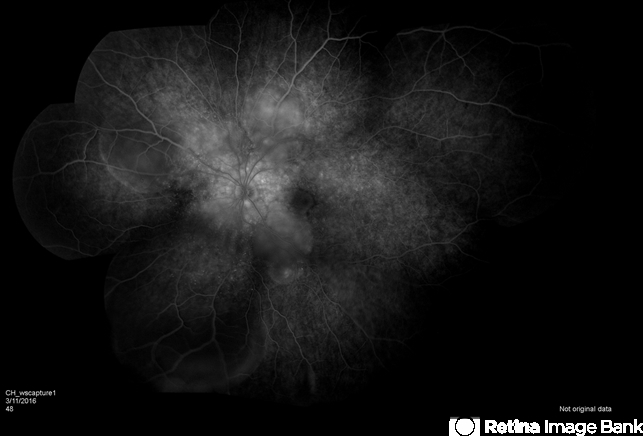

- edema, Vogt-Koyanagi-Harada

- VKH